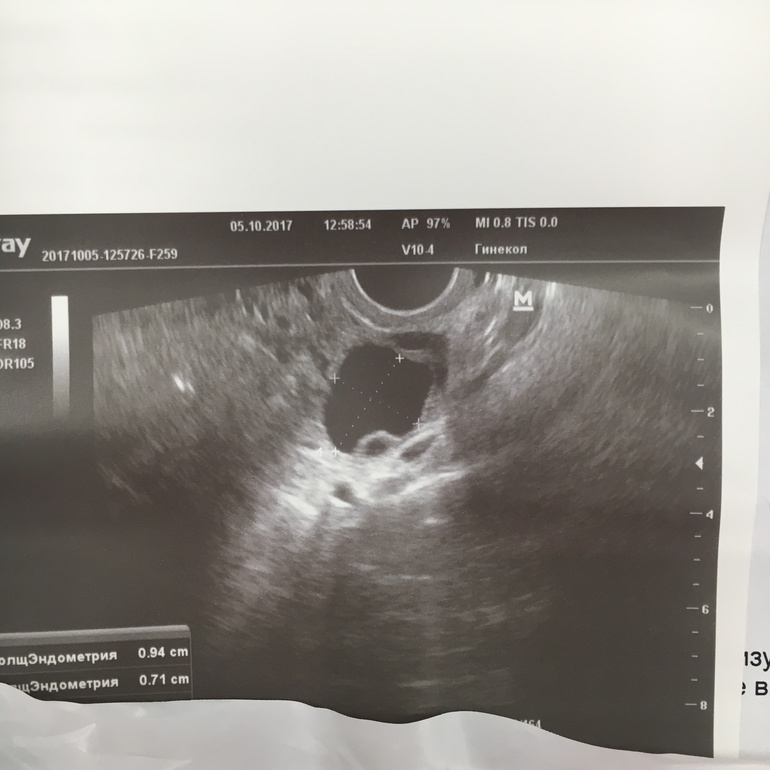

Только что пришла с фолликулометрии, что мы имеем : ДФ аж 22 мм, яйцеклетка есть, главное, чтобы не перерос!!! Может есть какие-нибудь хитрости, чтобы точно лопнул???

Эндометрий : 9,5 мм, НО(!) врач сказала, что он до сих пор соответствует первой фазе, но, может за день догнать.

можно! сейчас прикреплю фото :)

Большой фолик и округлость снизу это и есть ЯК :)

вот уж этого я не знаю, продвинутый или нет))) я 4 раза ходила на фолликулометрию в этом месяца и точно знаю, как мой фолик выглядит)))) до последнего УЗИ никаких округлых штук в нем не было

я может как-то не так изъясняюсь (не знаток, честно) , но, моя узист сказала, что это как раз то, что из фолика выходит))) даже сделала на этом акцент))